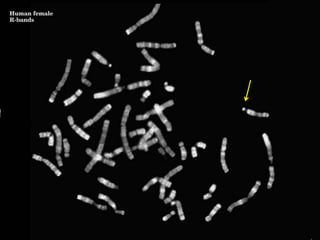

R banding

• Used to identify the

X chromosome abnormalities

• Heat chromosomes before

staining with Giemsa

• Light and dark bands

are reversed